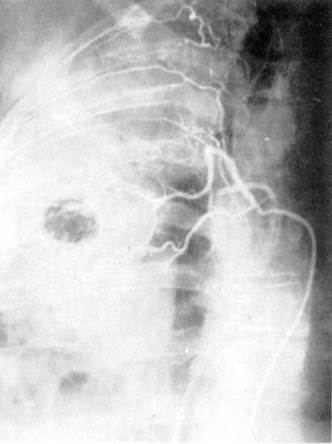

Рис. 6. Ангиопульмонография.

![]() |

а — артериальная фаза; б — капиллярная фаза; в — венозная фаза.